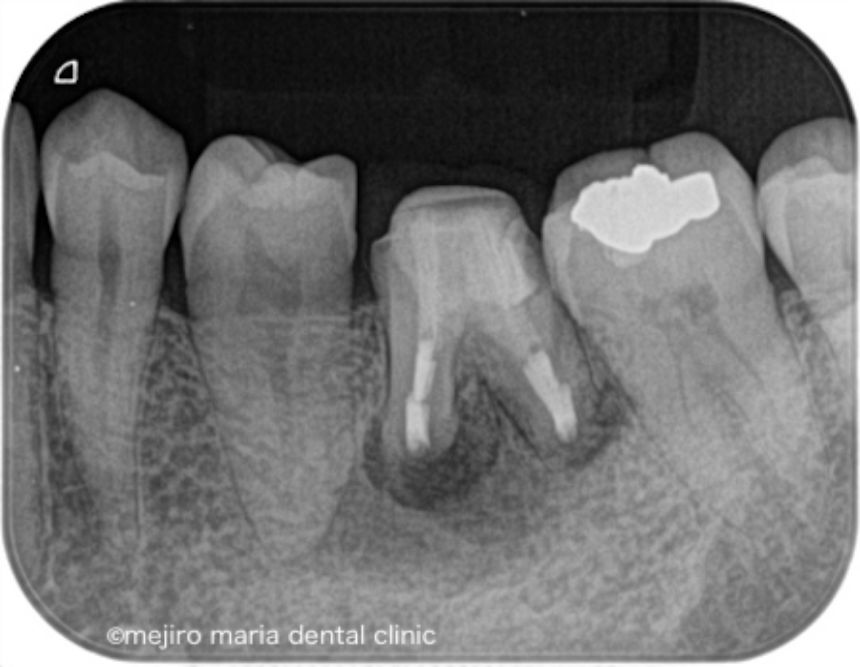

治療後の様子

術後3ヶ月の経過観察では、歯肉の腫れや噛んだときの違和感、痛みは消失し予後良好と判断しました。引き続き最終補綴処置(被せ物)の製作を行い2年間の経過観察に移行することとなりました。